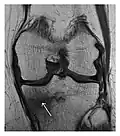

Figure 1: A 56-year-old woman presenting with left knee pain after a fall. (a) Initial anteroposterior radiograph was considered normal, however, subtle cortical disruption of the anterior rim of the medial tibial plateau, medial to the tibial spine, is noted (arrow). (b) Coronal T1-weighted MRI confirms the cortical disruption (arrow) and shows extensive fracture through the proximal tibia. (c) Coronal proton density-weighted image with fat saturation shows extensive edema in the subchondral bone. Note also hypersignal adjacent to the medial collateral ligament corresponding to a grade I sprain (arrowheads).[1]

Occult osseous injuries may result from a direct blow to the bone by compressive forces of adjacent bones against one another or by traction forces during an avulsion injury. Lesions in the tibial plateau, hip, ankle, and wrist are often missed. In a tibial plateau fracture, any disruption of the posterior and anterior cortical rims of the plateau should be sought. Impaction of subchondral bone will appear as an increased sclerosis of the subchondral bone (Figure 1). In the hip, posterior acetabular fractures also present subtle radiographic findings. The acetabular lines should then be carefully examined keeping in mind that the posterior rim, which is harder to see on X-rays, is more frequently fractured than the anterior rim (Figure 2). In the wrist, detection of carpal bone fractures is often challenging, with up to 18% of scaphoid fractures radiographically occult. Carpal fractures, especially the scaphoid, are associated with the risk of avascular necrosis. In apparently normal wrist radiographs from symptomatic patients, if there is history of a fall on an outstretched hand with pain in the anatomic snuffbox, suggesting scaphoid injury, the initial examination with posteroanterior, lateral, and pronation oblique views must be complemented by other specific views such as supination oblique and the "scaphoid" view A careful examination of cortices for evidence of discontinuity or offset and cancellous bone for lucency is necessary (Figure 3).[1]